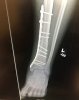

amazing what can be done with a cordless screwdriver and some coated deck screws!I hope they used the same Terminator type shit on Nurk that they did with THE HCP Jr.

I AM Mexican remember.amazing what can be done with a cordless screwdriver and some coated deck screws!

ok...so add in stucco and mortarI AM Mexican remember.

More like Bondo.ok...so add in stucco and mortar

Did you do that yourself?I hope they used the same Terminator type shit on Nurk that they did with THE HCP Jr.

Pardon my ignorance, but when you have screws or plates etc put into you like this, are they eventually removed?

Usually they are kept inside. There are some rare circumstances that will cause them to have to be removed.Pardon my ignorance, but when you have screws or plates etc put into you like this, are they eventually removed?